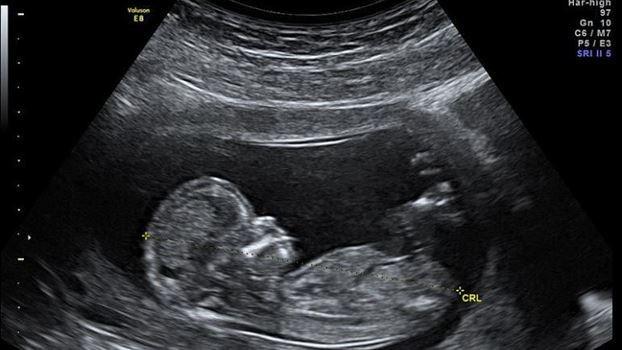

يوم الجمعة الفائت أسعفت المرأة الثمانينية إلى المستشفى وهي تعاني من اضطراباتٍ حادّة في المعدة، وبعد إجراء صور الأشعة وجد الأطباء "طفلاً متحجراً". هذه الظاهرة النادرة من نوعها تسمّى بـ "الجنين المكلّس" أو Lithopedion وهي عندما ينمو الجنين ويموت خارج الرحم. في هذه الحالة، لا يستطيع الجسم التخلّص من الجنين فيُغطى هذا الأخير بطبقةٍ من الكالسيوم للحماية.

الطبيب النسائي في المستشفى الذي نُقلت إليه يؤكّد أنّ صور الأشعة تُظهر وجه الجنين، عظامه، ذراعيه، رجليه، ضلوعه وحتى عاموده الفقري. "من المعتقد أن يكون الجنين قد تُوفي خلال الأسابيع الـ 20 والـ 28 من الحمل" يضيف الطبيب.